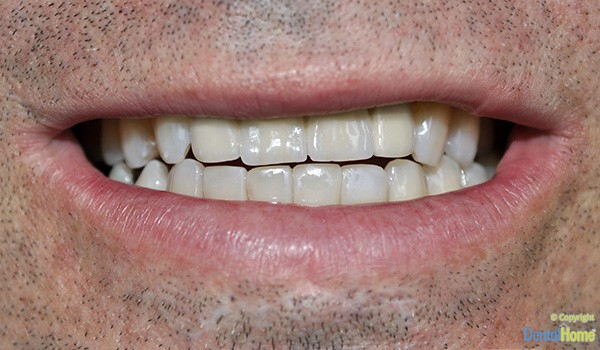

Galería de imágenes de coronas y puentes fijos